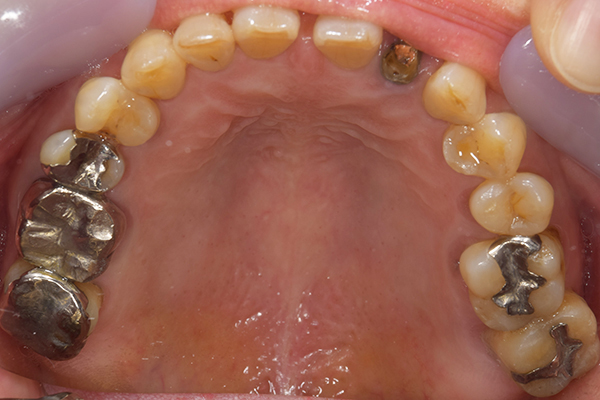

ケース2(自費の総入れ歯と部分入れ歯)

上下の入れ歯が外れやすくなったということでいらっしゃいました。 顎の骨はしっかりしていましたので、精密な型取りさえすればしっかりした入れ歯がつくれると思いました。 また下には6本歯が残っていましたが、虫歯になっている歯もありました。 かぶせ物のなかで大きな虫歯があった歯があり、1本だけ残せない状態でした。

上の入れ歯は確かに吸着は甘くなっていました。 また下の入れ歯はバネの一部が壊れており、安定感がなくなっていました。

精密な型取りの後、噛み合わせのチェックをしていきました。 かぶせ物も同時に作っていきました。

歯を並べた後、かぶせ物のフレーム作ってもらいました。先に歯を並べて理想の位置を決めておくことが大切です。

完成した入れ歯とかぶせ物です。 入れ歯への寛容度が高い患者様でしたので、 金属は使用せず、プラスチックのみで上は仕上げました。 下顎も歯は1本減ってしまいましたが、しっかり 入れ歯が維持できる様な構造にしました。

お口の中に入れた状態です。 見た目も最初とほとんど変わることなく作成できました。 維持や吸着に関しても問題ないようでした。

年齢 80歳・女性

主訴 上下の入れ歯が外れやすくなった

治療期間 3ヶ月

治療費 .メタルボンドクラウン:550,000円

.義歯:990,000円(税込、上下)

治療方針 長年使ってきた義歯の人工歯が磨耗し、臼歯部での咬合がすくなくなり、入れ歯の安定も悪くなり、あたりどころが悪くなって痛みが出ている。 そのため、入れ歯を上下作りかえる必要がある。

治療内容 過去に治療を行ったことのある歯が再度虫歯になってしまっているところがあり、すでに残せない状態にまでなっていたため、歯を一本抜歯した。 その後、かぶせ物と入れ歯を同時に作成していった。

特記事項 歯を抜いた後は、2〜3ヶ月歯ぐきの回復を待ってから入れ歯を作るため、待機期間があります。その間、古い入れ歯を調整しながらそのまま使うか、新し物をつくっておく必要があります。ただし、入れ歯は保険治療で作成する場合、6ヶ月は新しいものが作れないという決まりがあるので保険で全て作りたい場合は注意が必要です。